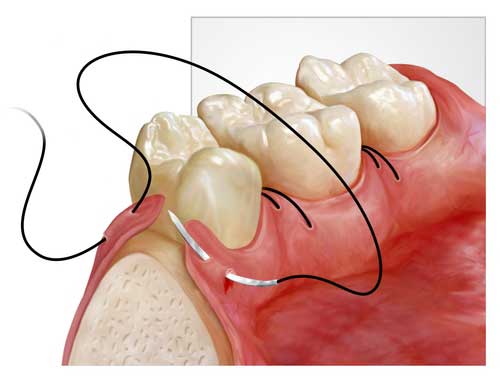

My surgical procedure for insertion of dental implants was easy and short despite what I expected before.

there were swelling and a little pain for two days after the surgery; however I could tolerate the pain by using analgesic drugs and by considering the doctor's orders. now I can eat easily and masticate my favorite foods perfectly.

Mr Rezaey, Implant Surgery Patient